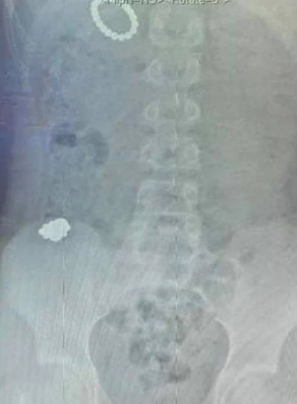

Inglaterra.- Un menor de 12 años tuvo que ser operado de emergencia tras tragarse 54 imanes como un “experimento”.

Los hechos se registraron en el Hospital Royal de Manchester, en Inglaterra, cuando el menor identificado como Rhiley le comentó a su mamá Paige Ward que se había comido estos objetos cuatro días después de que no pudo expulsarlos, por lo que ella decidió trasladarlo al nosocomio.

El menor tuvo que ser intervenido de urgencia y los médicos pudieron extraerle exitosamente los 54 imanes que se tragó, y tuvo que permanecer en cama para recuperarse, así mismo, se señaló que duró 10 días vomitando un líquido verde causado por una fuga intestinal, lo que lo llevó a ser alimentado por sonda.